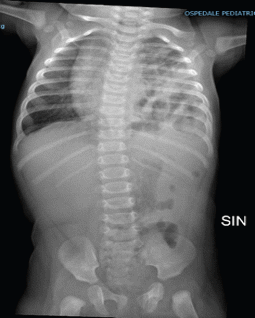

Alla luce della storia clinica veniva eseguita nuova ecografia addome che mostrava presenza di immagine di “whirlpool” in regione para-aortica sinistra ed evidenza di anse intestinali stirate cranialmente in cavità toracica sinistra. A completamento diagnostico veniva eseguita radiografia di torace e addome (Figura 1) che mostrava anse intestinali distese (in parte dal gas), che occupavano pressoché completamente la cavità toracica omolaterale; il polmone sinistro, disventilato e distelettasico, era dislocato cranialmente e l'immagine cardio-mediastinica presentava una modesta dislocazione verso destra.

I reperti di imaging apparivano suggestivi per volvolo intestinale in ernia diaframmatica sinistra. Veniva pertanto sottoposta ad intervento urgente di riduzione dell'ernia e riparazione della breccia diaframmatica, senza complicanze postchirurgiche. La radiografia del torace postoperatoria non mostrava anse intestinali in cavità toracica a sinistra e la paziente veniva dimessa in buone condizioni generali.